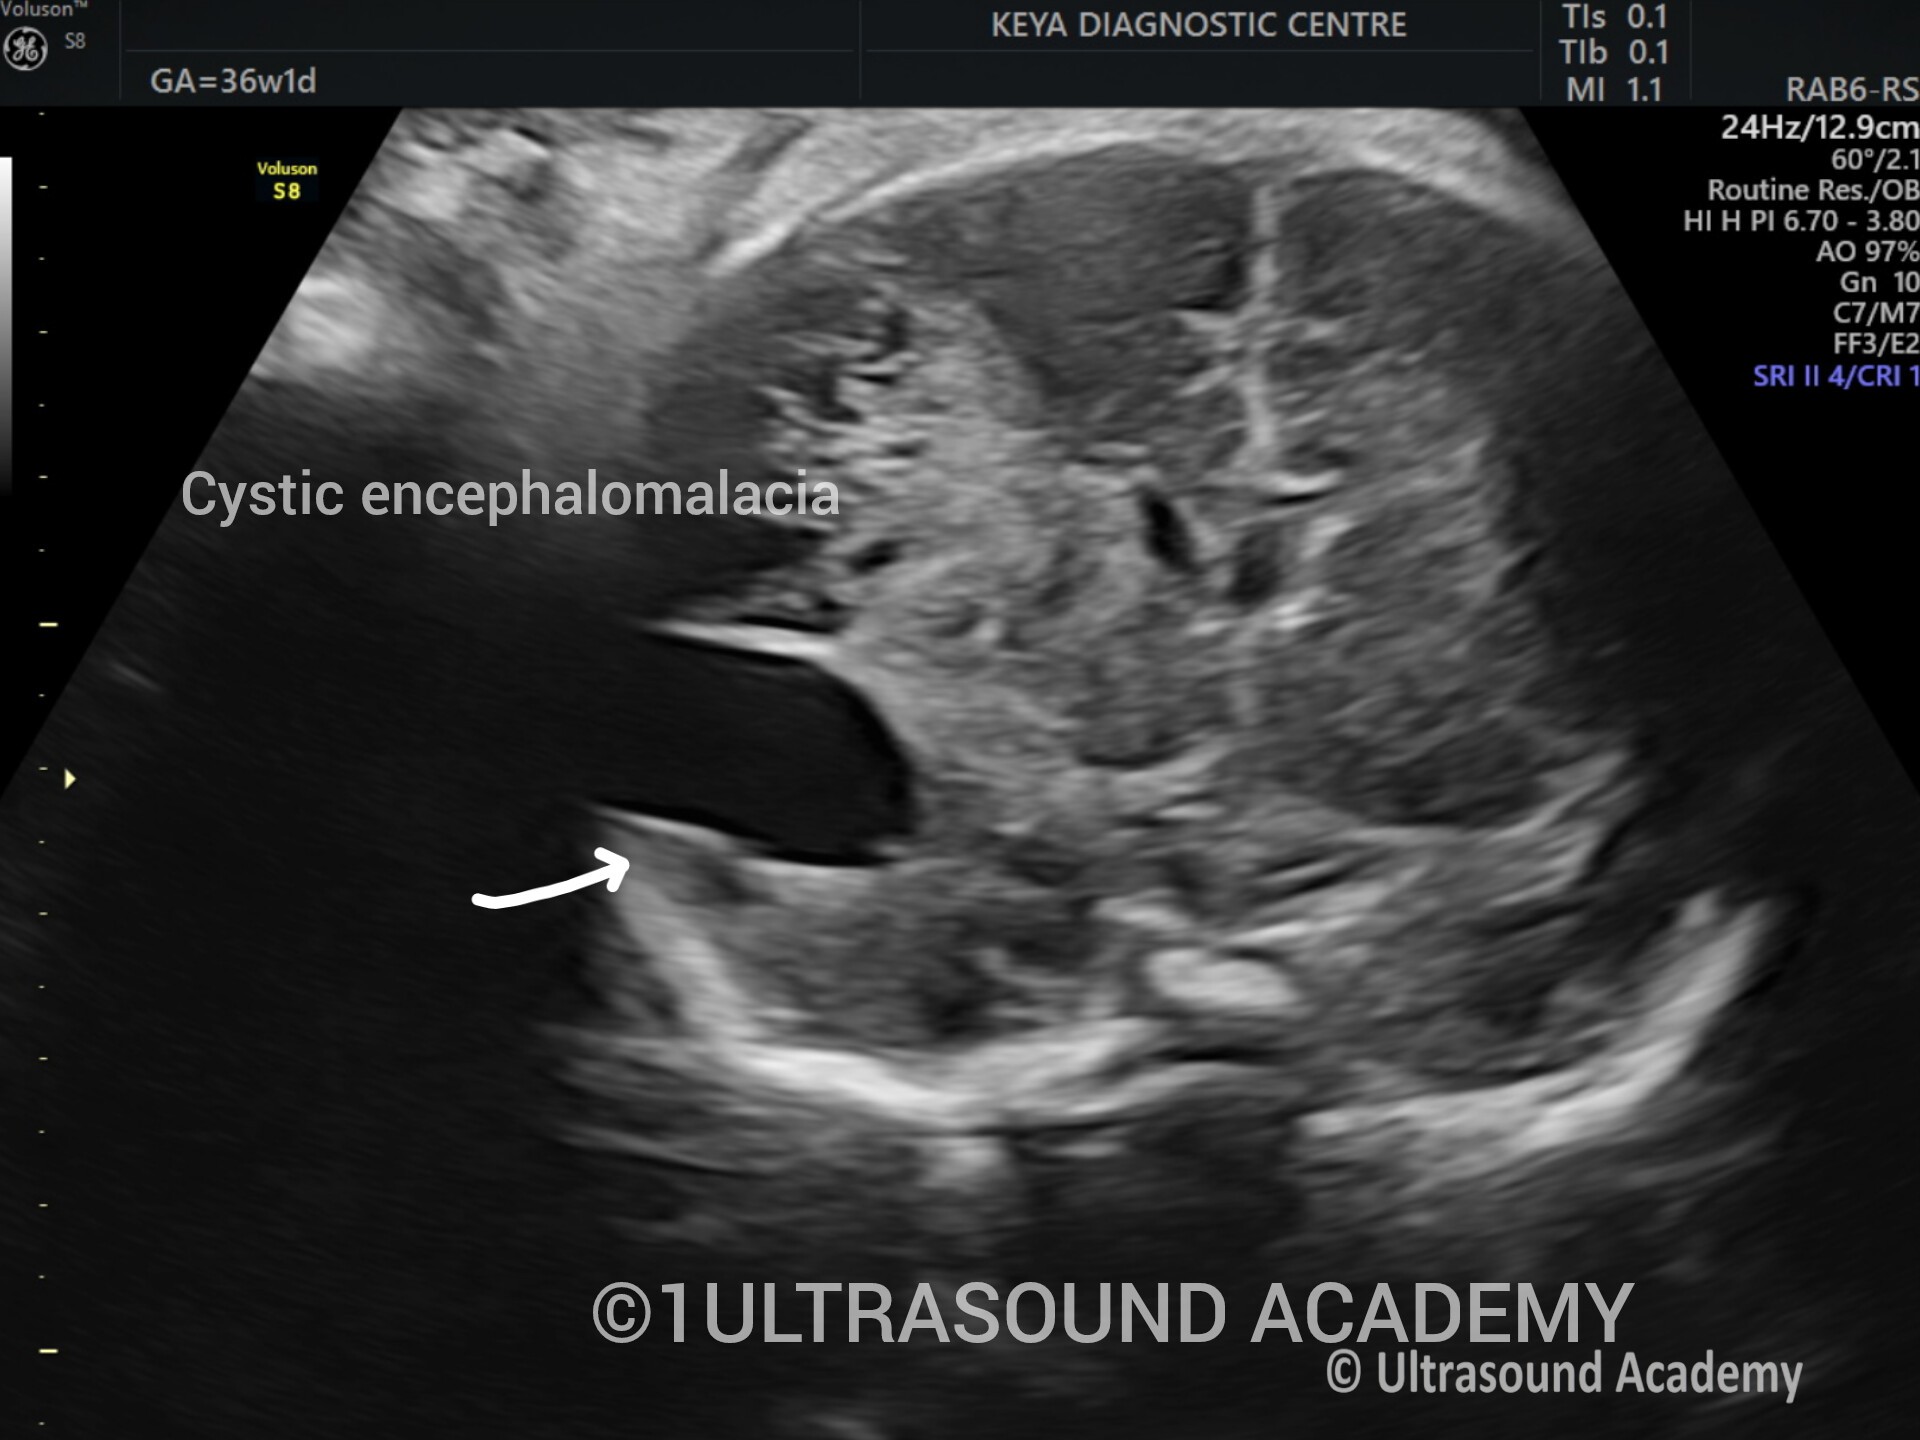

BRAIN HEMORRAHAGE OR INFRACT– Case By Dr. Nitin Jadhav